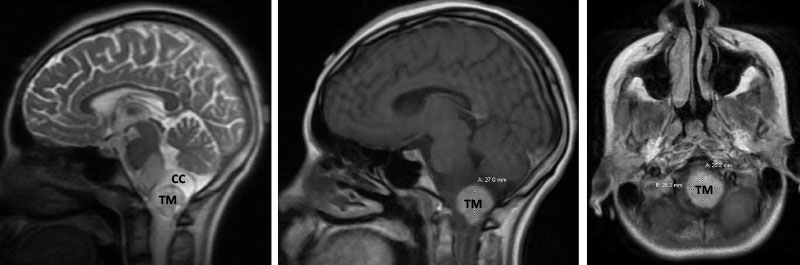

Figure 1. Brain MRI showing tumor mass (TM) with cystic component (CC) and edema (T2-weighted MRI, left) in the lower brainstem and upper cervical cord. Mass with contrast enhancement (post-contrast T1-weighted MRI, middle and right).

A teenage boy presented with 6 months of weight loss and difficulty swallowing. A contrast-enhancing mass in the brainstem and upper cervical cord was found which was suspicious of a symptomatic hemangioblastoma (Figure 1).

Symptoms from the slowly growing tumor stem from mass effect caused by the cystic component and the tumor. Contrast-enhanced brain MRI shows a hypervascular tumor. However, the exact location of the tumor in terms of intra- or extramedullary or intraand extramedullary can be difficult to determine on imaging and may only be clarified during surgery5.